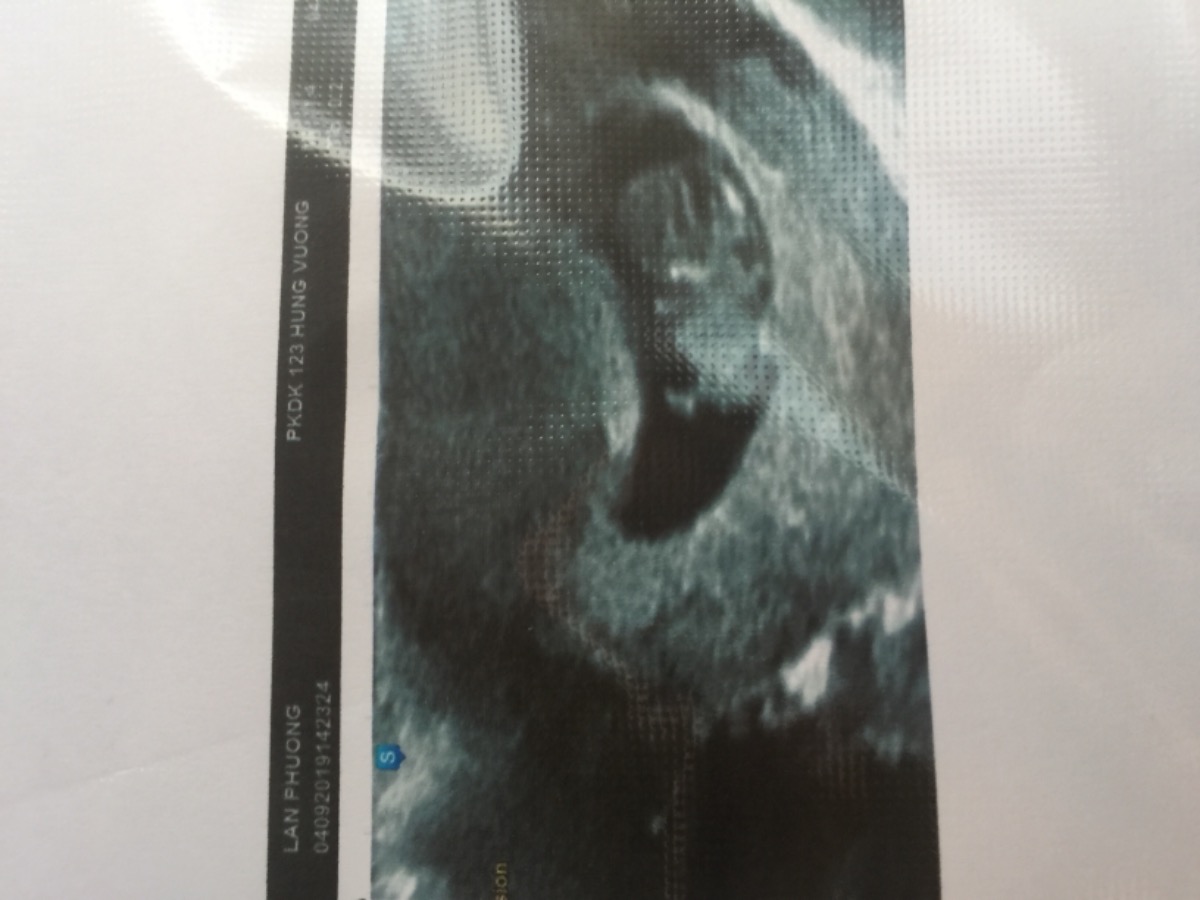

Em bầu 9 tuần nay do bị cảm nên đi khám bs bảo cảm nhẹ cho xịt mũi và súc miệng thôi.Khỏi siêu âm mà em kêu thôi siêu âm luôn coi con em có sao không ạ.thì siêu âm có túi dịch dưới túi thai.E không thấy đau bụng mấy cũng k ra huyết.Bs cho thuốc dưỡng về.Có ai bị giống e không ạ có sao k các m